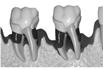

この図をご覧下さい。

歯は歯槽骨という骨に支えられています。

あなたの歯がまだしっかりとしてグラグラともしていないのは、

この歯を支えている骨がしっかりしているからなのです。

歯周病は骨の病気。歯は歯槽骨とう骨に埋まっているのです

骨はつまり基礎です。